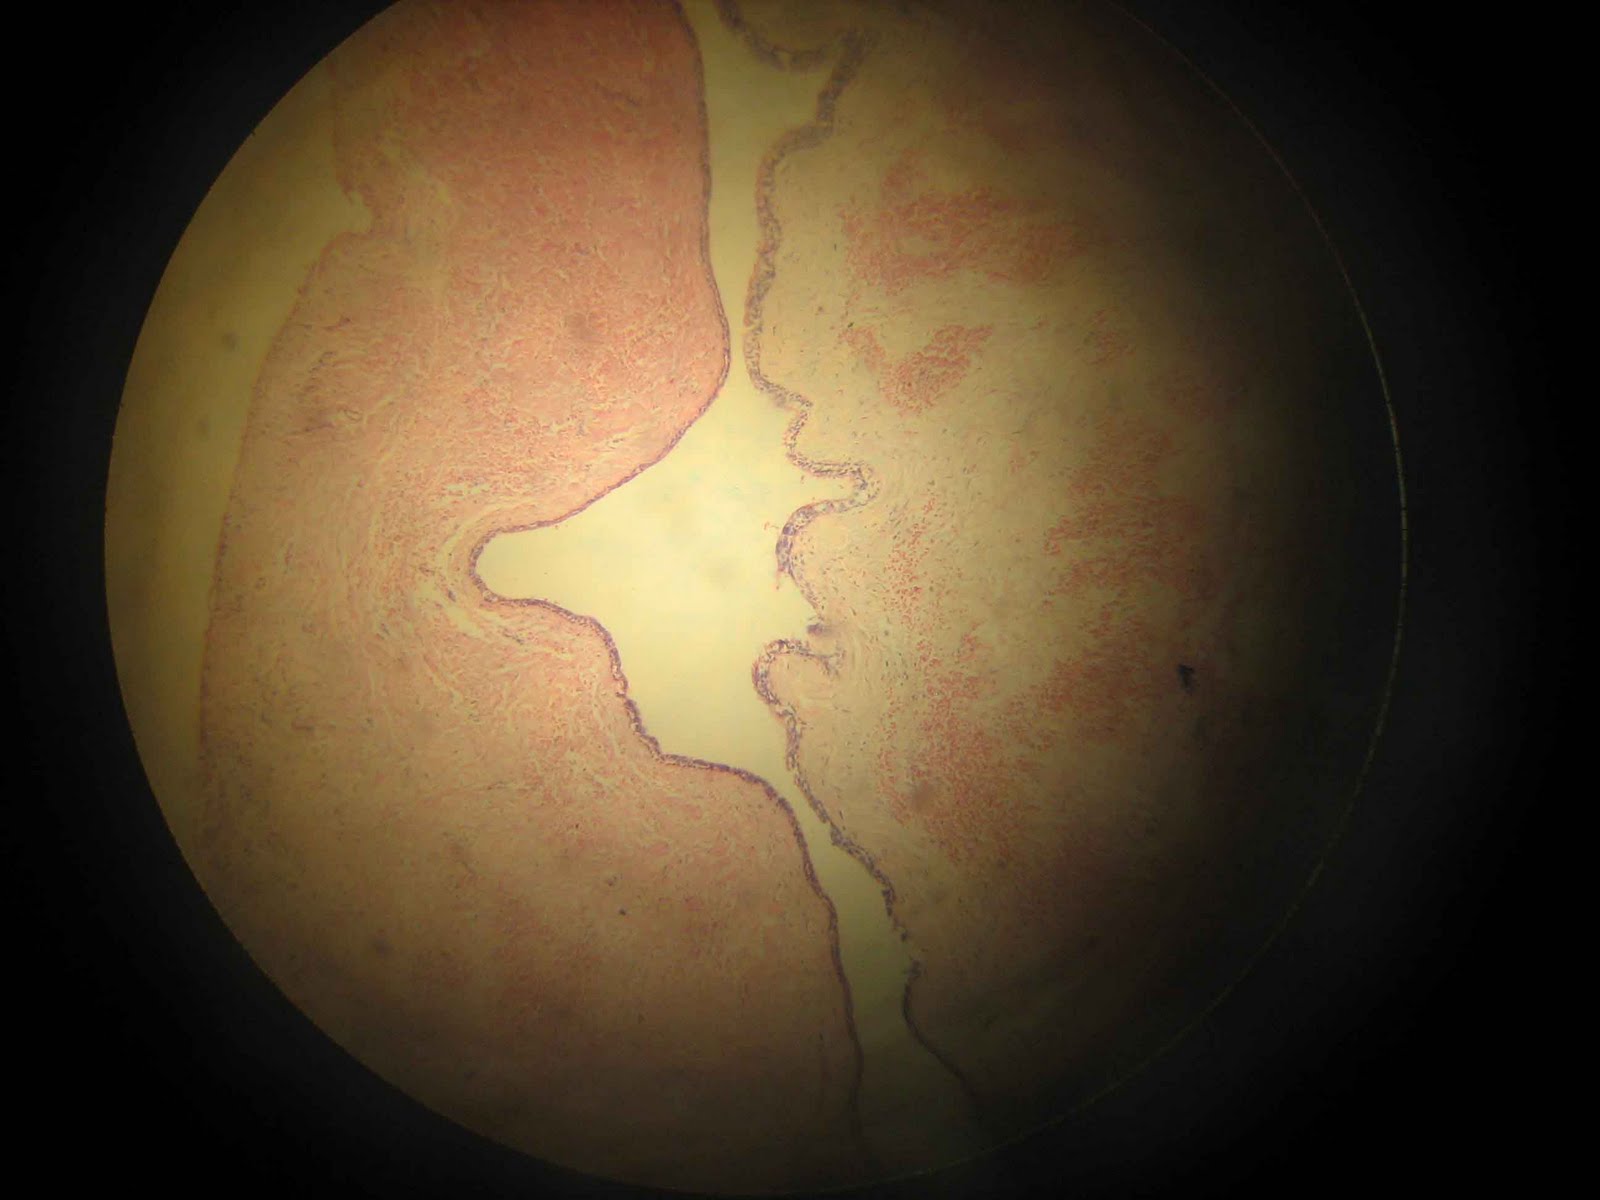

Dentigerous Cyst

· Lining of dentigerous cyst typycally consist of thin,sometimes bilaminar,stratified epithellium,frequently with numerous mucous cells.

· Fibrous wall similar as Radicular cyst but inflammatory changes are typicaly absent.